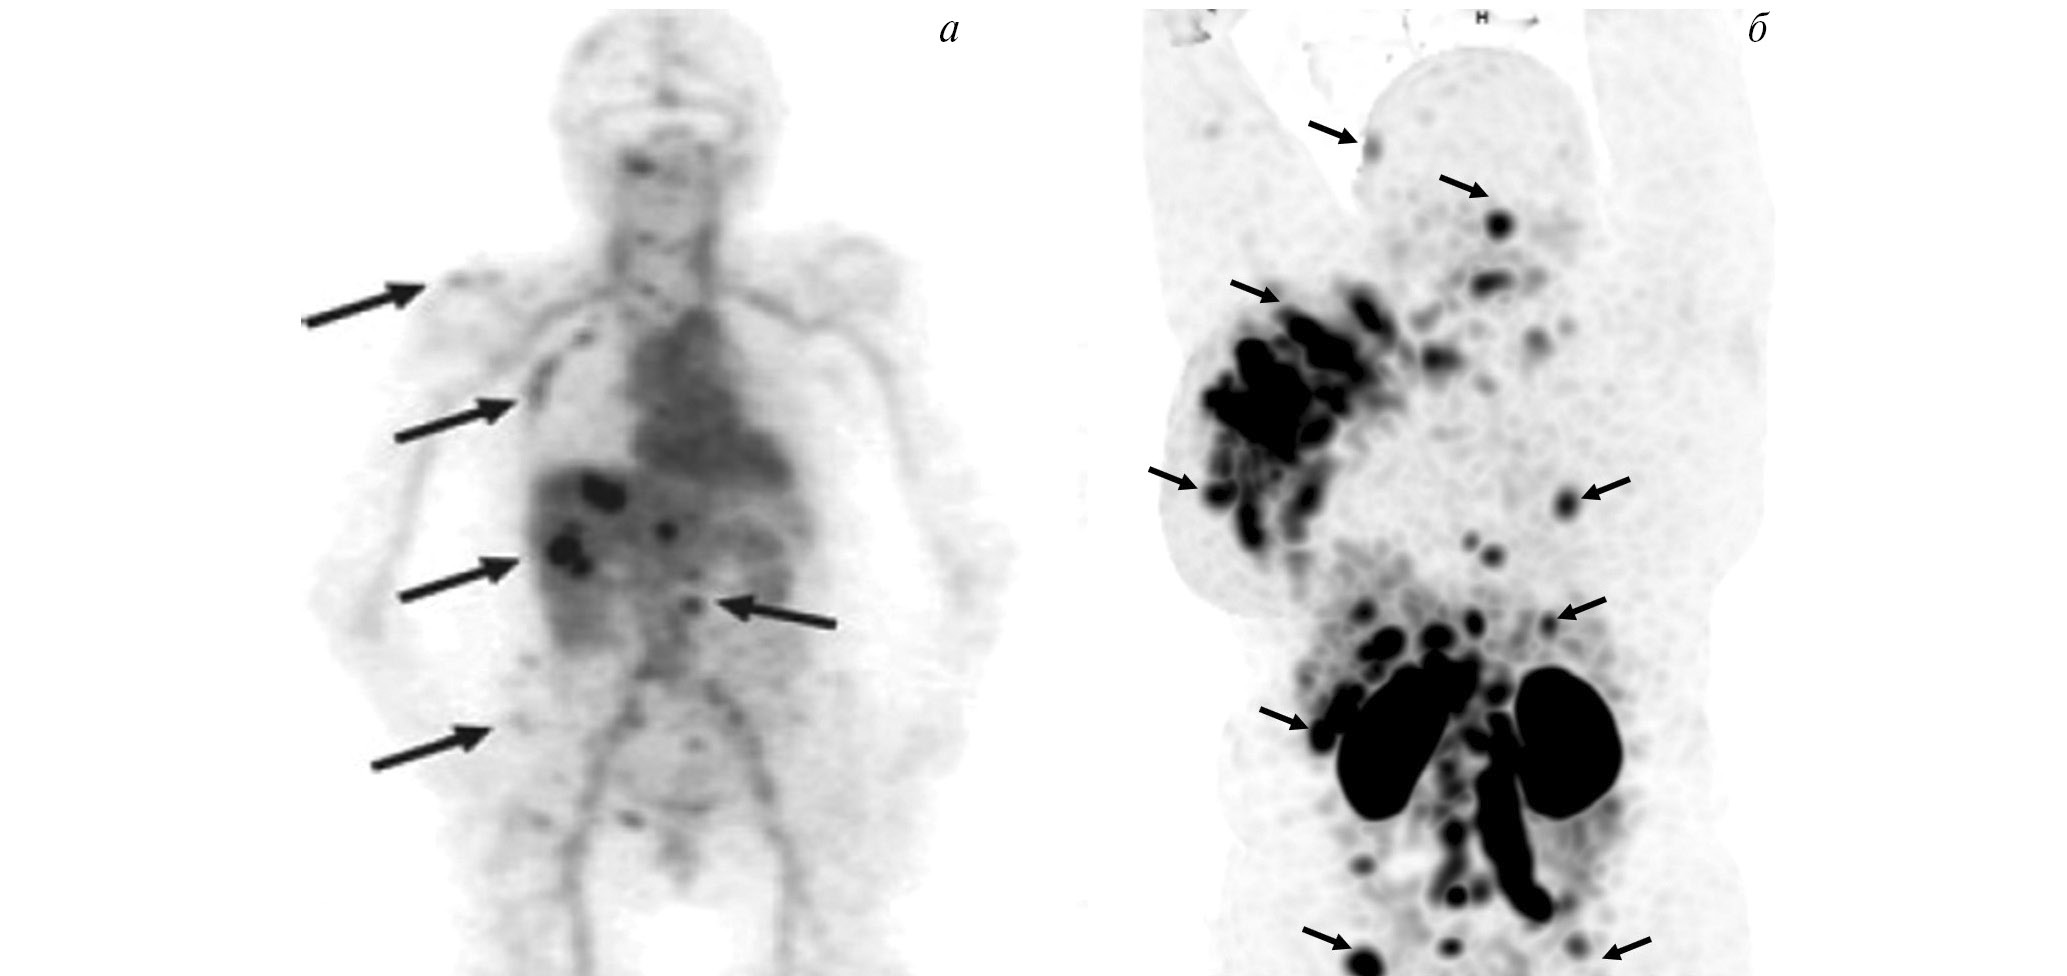

Рис. 1. ПЭТ-изображение пациентки с HER2/neu-позитивным раком молочной железы, выполненное через 5 суток после введения 89Zr-транстузумаба (a), стрелками обозначены метастазы в печень и кости [12]; ОФЭКТ-изображение пациентки с HER2/neu-позитивным раком молочной железы через 2 ч после введения 99mTc-ADAPT6 (б), стрелками обозначены первичная опухоль, метастазы в лимфатические узлы, печень и кости

В мировой ядерной медицине для сцинтиграфии обычно применяют 111In-пентетреотид, или 111In-октреотид ([111In-DTPA]octreotide, OctreoScan, Tyco Healthcare, США; АО “Фармсинтез”, Россия). Основные показания к его использованию — стадирование, рестадирование и мониторинг лечения нейроэндокринных SSTR-позитивных опухолей. В последние годы 111In-пентетреотид служит для радионавигации при хирургическом лечении новообразований с гиперэкспрессией соматостатиновых рецепторов. К сожалению, физические характеристики индия-111 (длительный период полураспада, неоптимальный для регистрации на гамма-камере спектр излучения, высокая стоимость циклотронного производства) ограничивают его применение в радионуклидной диагностике. В связи с этим не подвергается сомнению актуальность создания в России меченного технецием-99м октреотида для ОФЭКТ-диагностики нейроэндокринных опухолей. Разработкой такого радиофармпрепарата в рамках проекта федеральной целевой программы “Фарма-2020” занимался ТПУ в сотрудничестве с НИИ онкологии Томского НИМЦ. Клинические испытания отечественного 99mТс-октреотида продемонстрировали его высокую эффективность при диагностике и стадировании НЭО (рис. 3). В настоящее время набор для приготовления этого РФЛП зарегистрирован в России под названием “Нейроскан, 99mТс”, а его производство налажено в ТПУ.

Рис. 3. ОФЭКТ/КТ с 99mТс-октреотидом пациента с нейроэндокринным раком лёгкого: а — конгломерат первичной опухоли и метастазов в лимфатические узлы; б — метастазы в кости; в – селезёнка